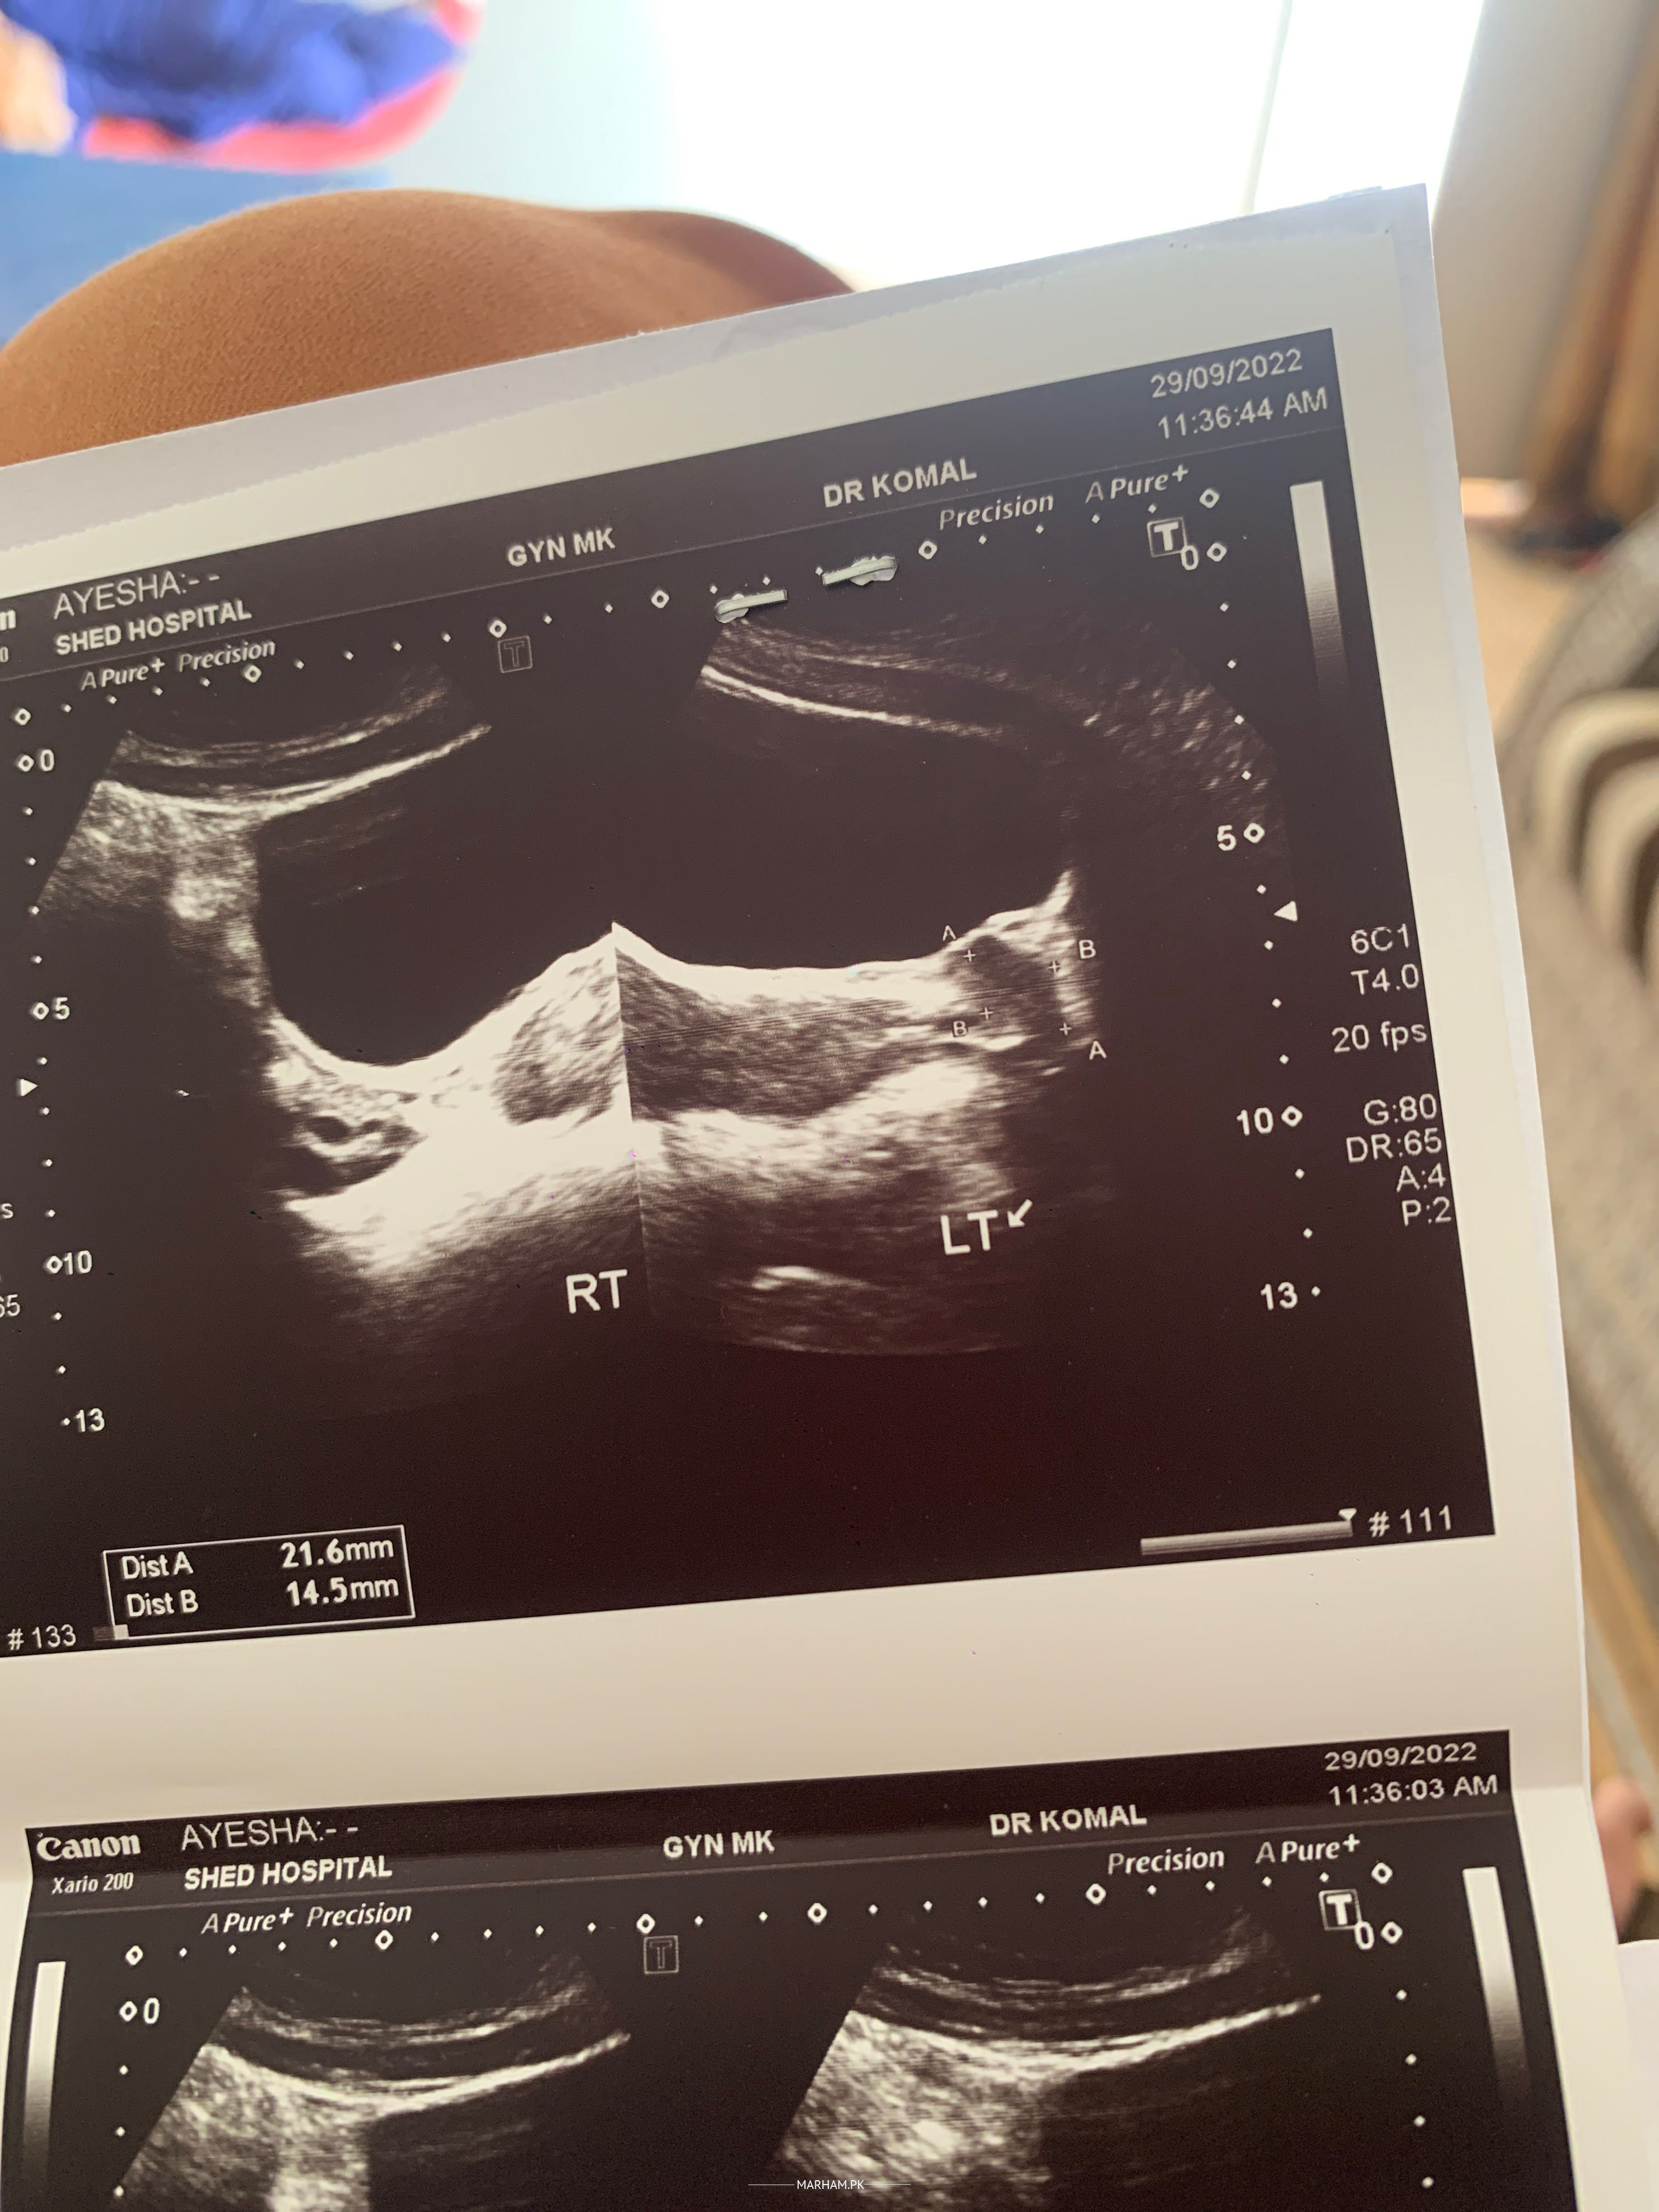

Kindly check my report and reply I’m in tension why is issue? Thankyou

Attach Photo here: